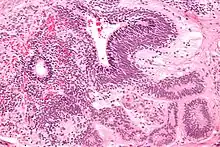

A micrograph showing a choriocarcinoma spread to the lung[13]

Choriocarcinomas are exceptionally rare which account for 2.1%-3.4% of all OGCTs.[14] Under gross examination, the syncytiotrophoblast cells are aligned in a plexiform arrangement with the mononucleated cytotrophoblast cells surrounding the foci of the hemorrhage.[1] Choriocarcinomas can be divided into gestational choriocarcinomas and non-gestational choriocarcinomas which have immunohistochemical differences.[15]